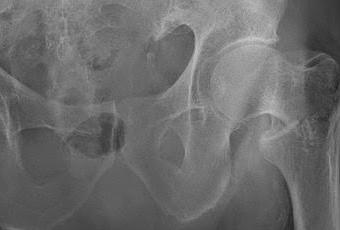

Se puede optar por esta técnica por el tipo de fractura que presenta el paciente, una fractura extracapsular (por fuera de la articulación en sí), en la parte baja del cuello del fémur.El resultado es el que os muestro en las radiografías. Se puede observar la restitución anatómica de la cadera con su clavo fijando la fractura. A su vez el tornillo que atraviesa el clavo es móvil, de tal manera que cuando el paciente empieza a caminar, que lo hace desde el segundo día tras la operación, la fractura se comprime y se cura antes. En 1 mes la fractura suele estar soldada ya, y la vida normal se suele recuperar en 2 meses desde la operación, aunque todo depende de la calidad de vida y movilidad previa del paciente.Las Rx se muestran abajo: